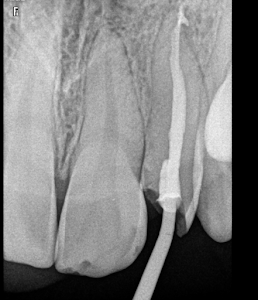

Welcome to our gallery

See how our company transforms ideas into reality. This gallery is a visual testament to our work and achievements.